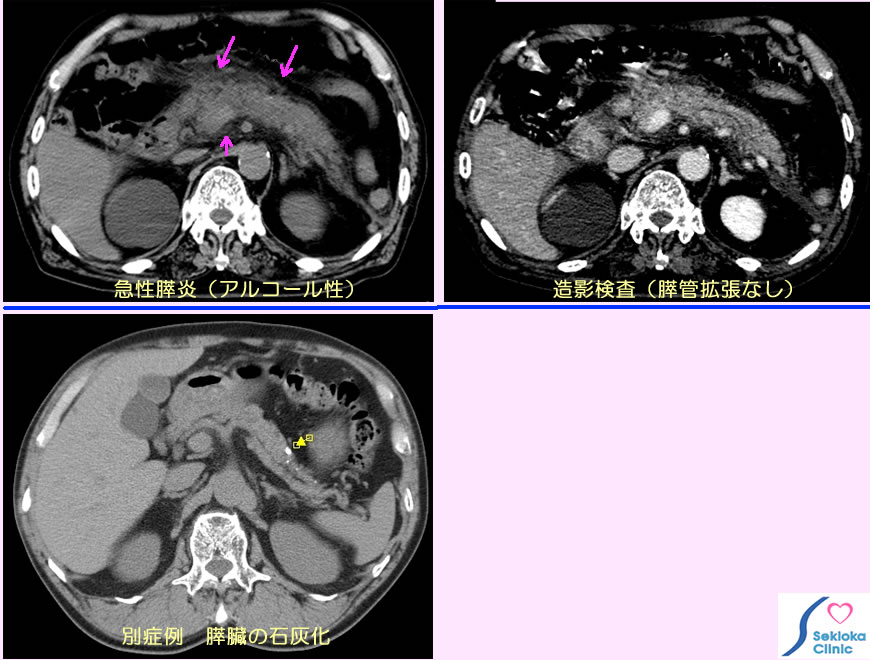

| 診断 | 超音波エコー検査、CTなどで殆ど診断できる。血液生化学検査(アミラーゼ・炎症反応・白血球)も有用な指標で併せて行われる。原因の検索には 膵臓の形態や膵管拡張、胆管拡張、石の存在など超音波エコー、CT、MRIなどが使われる。挿入のCT画像では膵臓の腫大と周囲の浮腫(矢印)を認める。右の画像から膵管拡張や胆管拡張は無く、飲酒によると推定。下段の比較参考画像は石灰化があるが浮腫・腫大のない膵臓である。 |